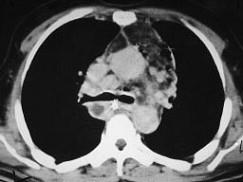

问题 男,64岁,患糖尿病,最近三天出现发热,伴颈静脉显露,结合CT图像,选择最可能的诊断 ( )

选项 A、恶性畸胎瘤 B、纵隔脓肿 C、纵隔淋巴瘤 D、侵袭性胸腺瘤 E、坏死性纵隔炎

答案 E